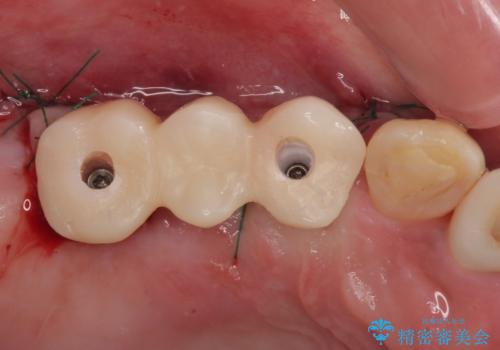

抜歯即時埋入インプラントによる補綴治療の特徴は、短期間であることや処置数が少ないことが挙げられます。また、表側の歯肉の陥凹を避けることができるというメリットがあります。しかしながら、今回は歯根破折の程度が酷く、やや膨らみを失うこととなりましたが、スムーズに治療を終えることができました。

臼歯部は前歯以上に炎症が酷く、抜歯即時埋入不可と判断されましたが、従来法よりは短期間で終えることができました。